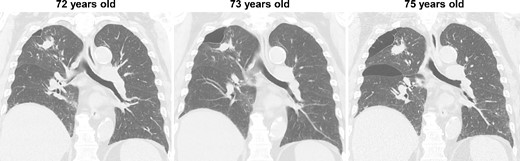

During the computed tomography (CT) scan of the 62-year-old patient, physicians did not point out infiltrating shadows in the right upper lobe caused by suspected pulmonary tuberculosis. Therefore, a chest CT scan was not performed until the patient developed a right pneumothorax at age 70. At 70 years old, the patient developed pneumothorax in his right lung; a CT scan revealed a 3.2 cm mass with satellite lesions in the right upper lobe, as well as pulmonary cysts on the peripheral side of the mass (Fig. 1). At this point, a retrospective review of the patient’s earlier CT images (at age 62 years) confirmed that there were some shadows indicative of pulmonary infiltration in the upper lobe of the right lung, although pulmonary cysts were not visible. The pulmonary cysts were considered to have caused the patient’s pneumothorax, which resolved following chest drainage. A bronchoscopy was performed after the pneumothorax improved, with brushing cytology and bronchoalveolar lavage cytology revealing no malignant cells. An acid-fast bacilli culture of the patient’s bronchoalveolar lavage fluid and the T-cell spot test for tuberculosis infection (T-SPOT.TB) were both negative. An 18F-fluorodeoxyglucose positron emission tomography/CT scan showed a maximum standard uptake value (SUVmax) of 1.8 in the lung mass. Since the lung mass was not suspected to be aggressively malignant [8], careful follow-up was performed, involving another CT scan. The lung mass was not enlarged; however, some growth of the pulmonary cysts was observed (Fig. 2).

CT imaging findings; at age 62, shadows suggesting pulmonary infiltration were present in the upper lobe of the patient’s right lung, but no pulmonary cysts were observed; at age 70, the patient developed spontaneous pneumothorax in his right lung; another scan revealed a 3.2 cm lung mass with satellite lesions in the upper lobe of the right lung, as well as pulmonary cysts on the peripheral side of the mass; at age 75, the patient experienced a relapse of the spontaneous pneumothorax in the same lung.

At 75 years old, the patient’s right spontaneous pneumothorax relapsed (Fig. 1). Exploratory surgery was performed to diagnose the lung mass and treat the pneumothorax. The lung mass and pulmonary cysts were excised (Fig. 3A and B). The lung mass was diagnosed as a granuloma with necrosis through analysis of frozen surgical biopsy sections, and a polymerase chain reaction (PCR) test for tuberculosis was positive. The operative time was 134 min, and the estimated blood loss was 15 ml. No postoperative air leakage was observed, and the patient’s chest drain tube was removed on postoperative Day 2. He was discharged on postoperative Day 12, following respiratory rehabilitation due to his obesity. The timeline of the patient’s clinical course is presented in Fig. 4.